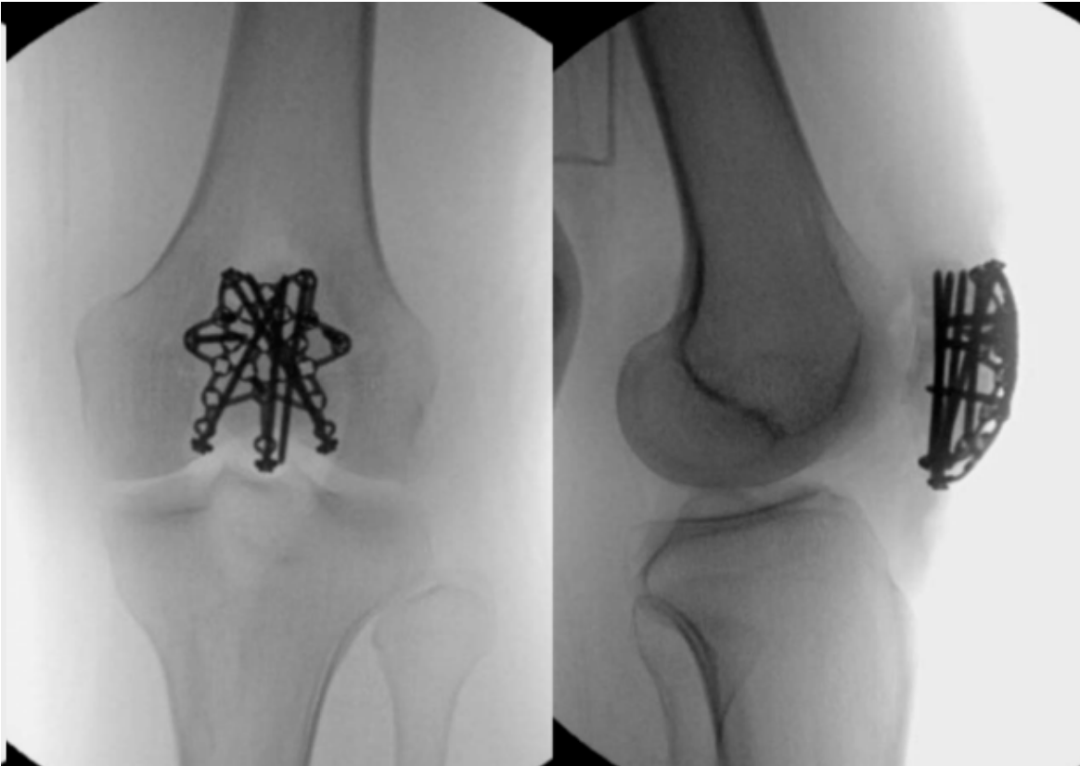

横行髌骨骨折(AO 34-C1)占所有髌骨骨折的23%。许多生物力学研究评估了在此类骨折形态中使用张力带钢丝(TBW)进行固定,TBW被广泛认为是这种"简单"骨折形态的金标准(见图1)。

图1. 展示了一个采用张力带钢丝(TBW)固定治疗的横行髌骨骨折示例。

张力带钢丝(TBW)背后的生物力学原理,是将作用于髌骨前表面的张力转化为关节面的压力,从而实现动态骨折块间加压。在传统的TBW(张力带钢丝)技术中,两根克氏针近端弯曲呈平行走向,随后将一根8字形环扎钢丝缠绕其上以提供稳定。对于粉碎性骨折和远端极骨折,可分别采用额外的环形环扎或减张环扎(McLaughlin)技术。